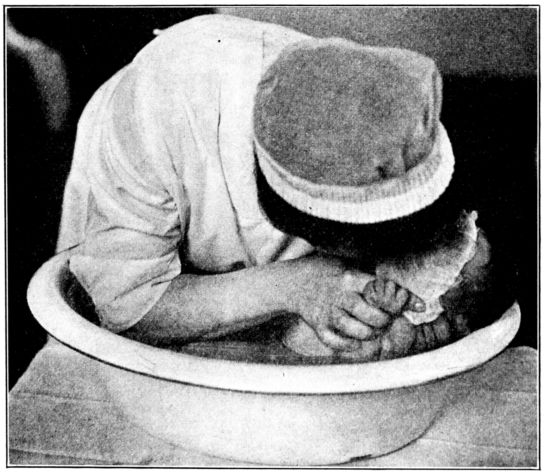

| 154. | Bathing the baby | 467 |